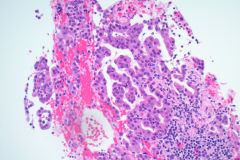

Specimen Type: FNA Station 4L, 4R Lymph Nodes, Modified Romanowsky smears, Papanicolaou smears, Thin Prep® Non-Gyn slide, H&E Cellient® Cell Block

Biopsy/Pathologic Diagnosis: Corresponding Surgical Pathology H&E Slides of Core Biopsy of 4R Lymph Node, Positive for Malignancy, Adenocarcinoma with malignant cells staining positive for TTF-1 and negative for GATA3 and SOX10. PD-L1 immunohistochemical staining is positive.

When reviewing the slides cytologically, there is moderate to high cellularity, with malignant cells present in three-dimensional cohesive groups as well as scattered single cells.1,7 Compared to the background population, these cells appear enlarged and demonstrate increased nuclear-to-cytoplasmic ratios, irregular nuclear borders and contours, and prominent nucleoli with variable chromatin patterns.1 Nuclear pleomorphism is present, and occasional multinucleated tumor cells can be identified.1 The cytoplasm is moderate in amount and appears vacuolated due to mucin production, which reflects glandular differentiation with extracellular mucin and necrotic debris present in the background.1,2 Overall, these cytologic findings are characteristic of an epithelial glandular cell malignancy. Because adenocarcinoma shares overlapping cytologic features with other poorly differentiated tumors, IHC stains such as TTF-1 and Napsin A are used to help confirm pulmonary origin.1,7